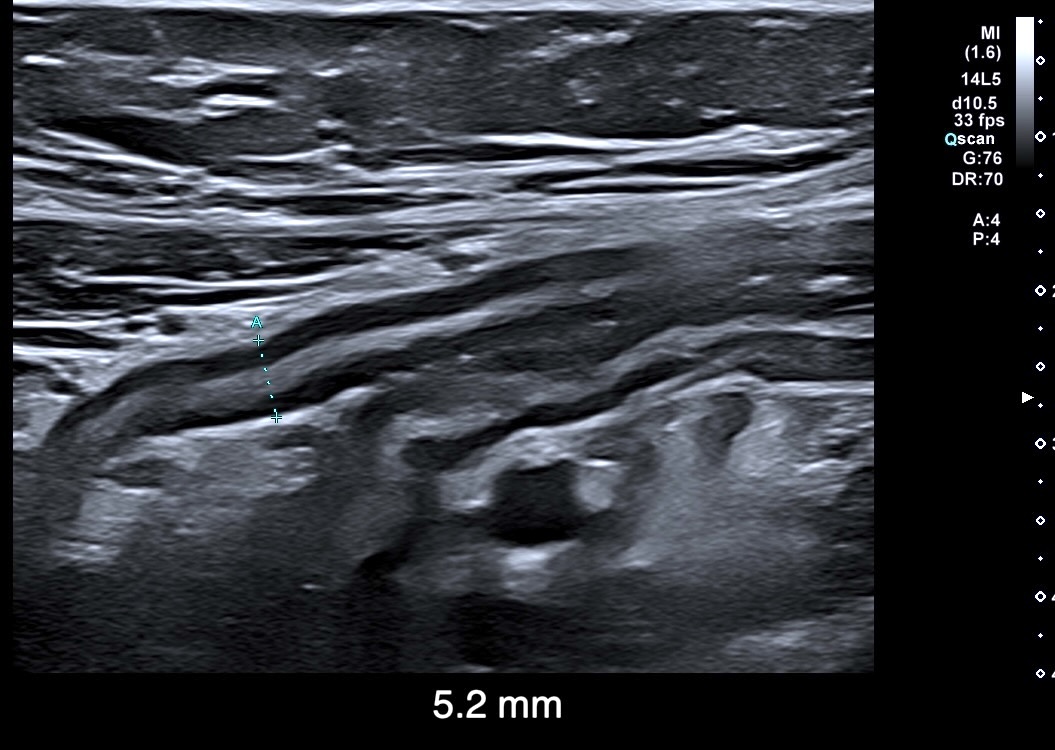

Exemple de paroi de 5 mm avec début de la disparition de la structure en couches (le contraste entre la muqueuse et la sous muqueuse est moins visible)

L'épaississement est encore plus important (8 mm), la surfacede la lumière devient irrégulière